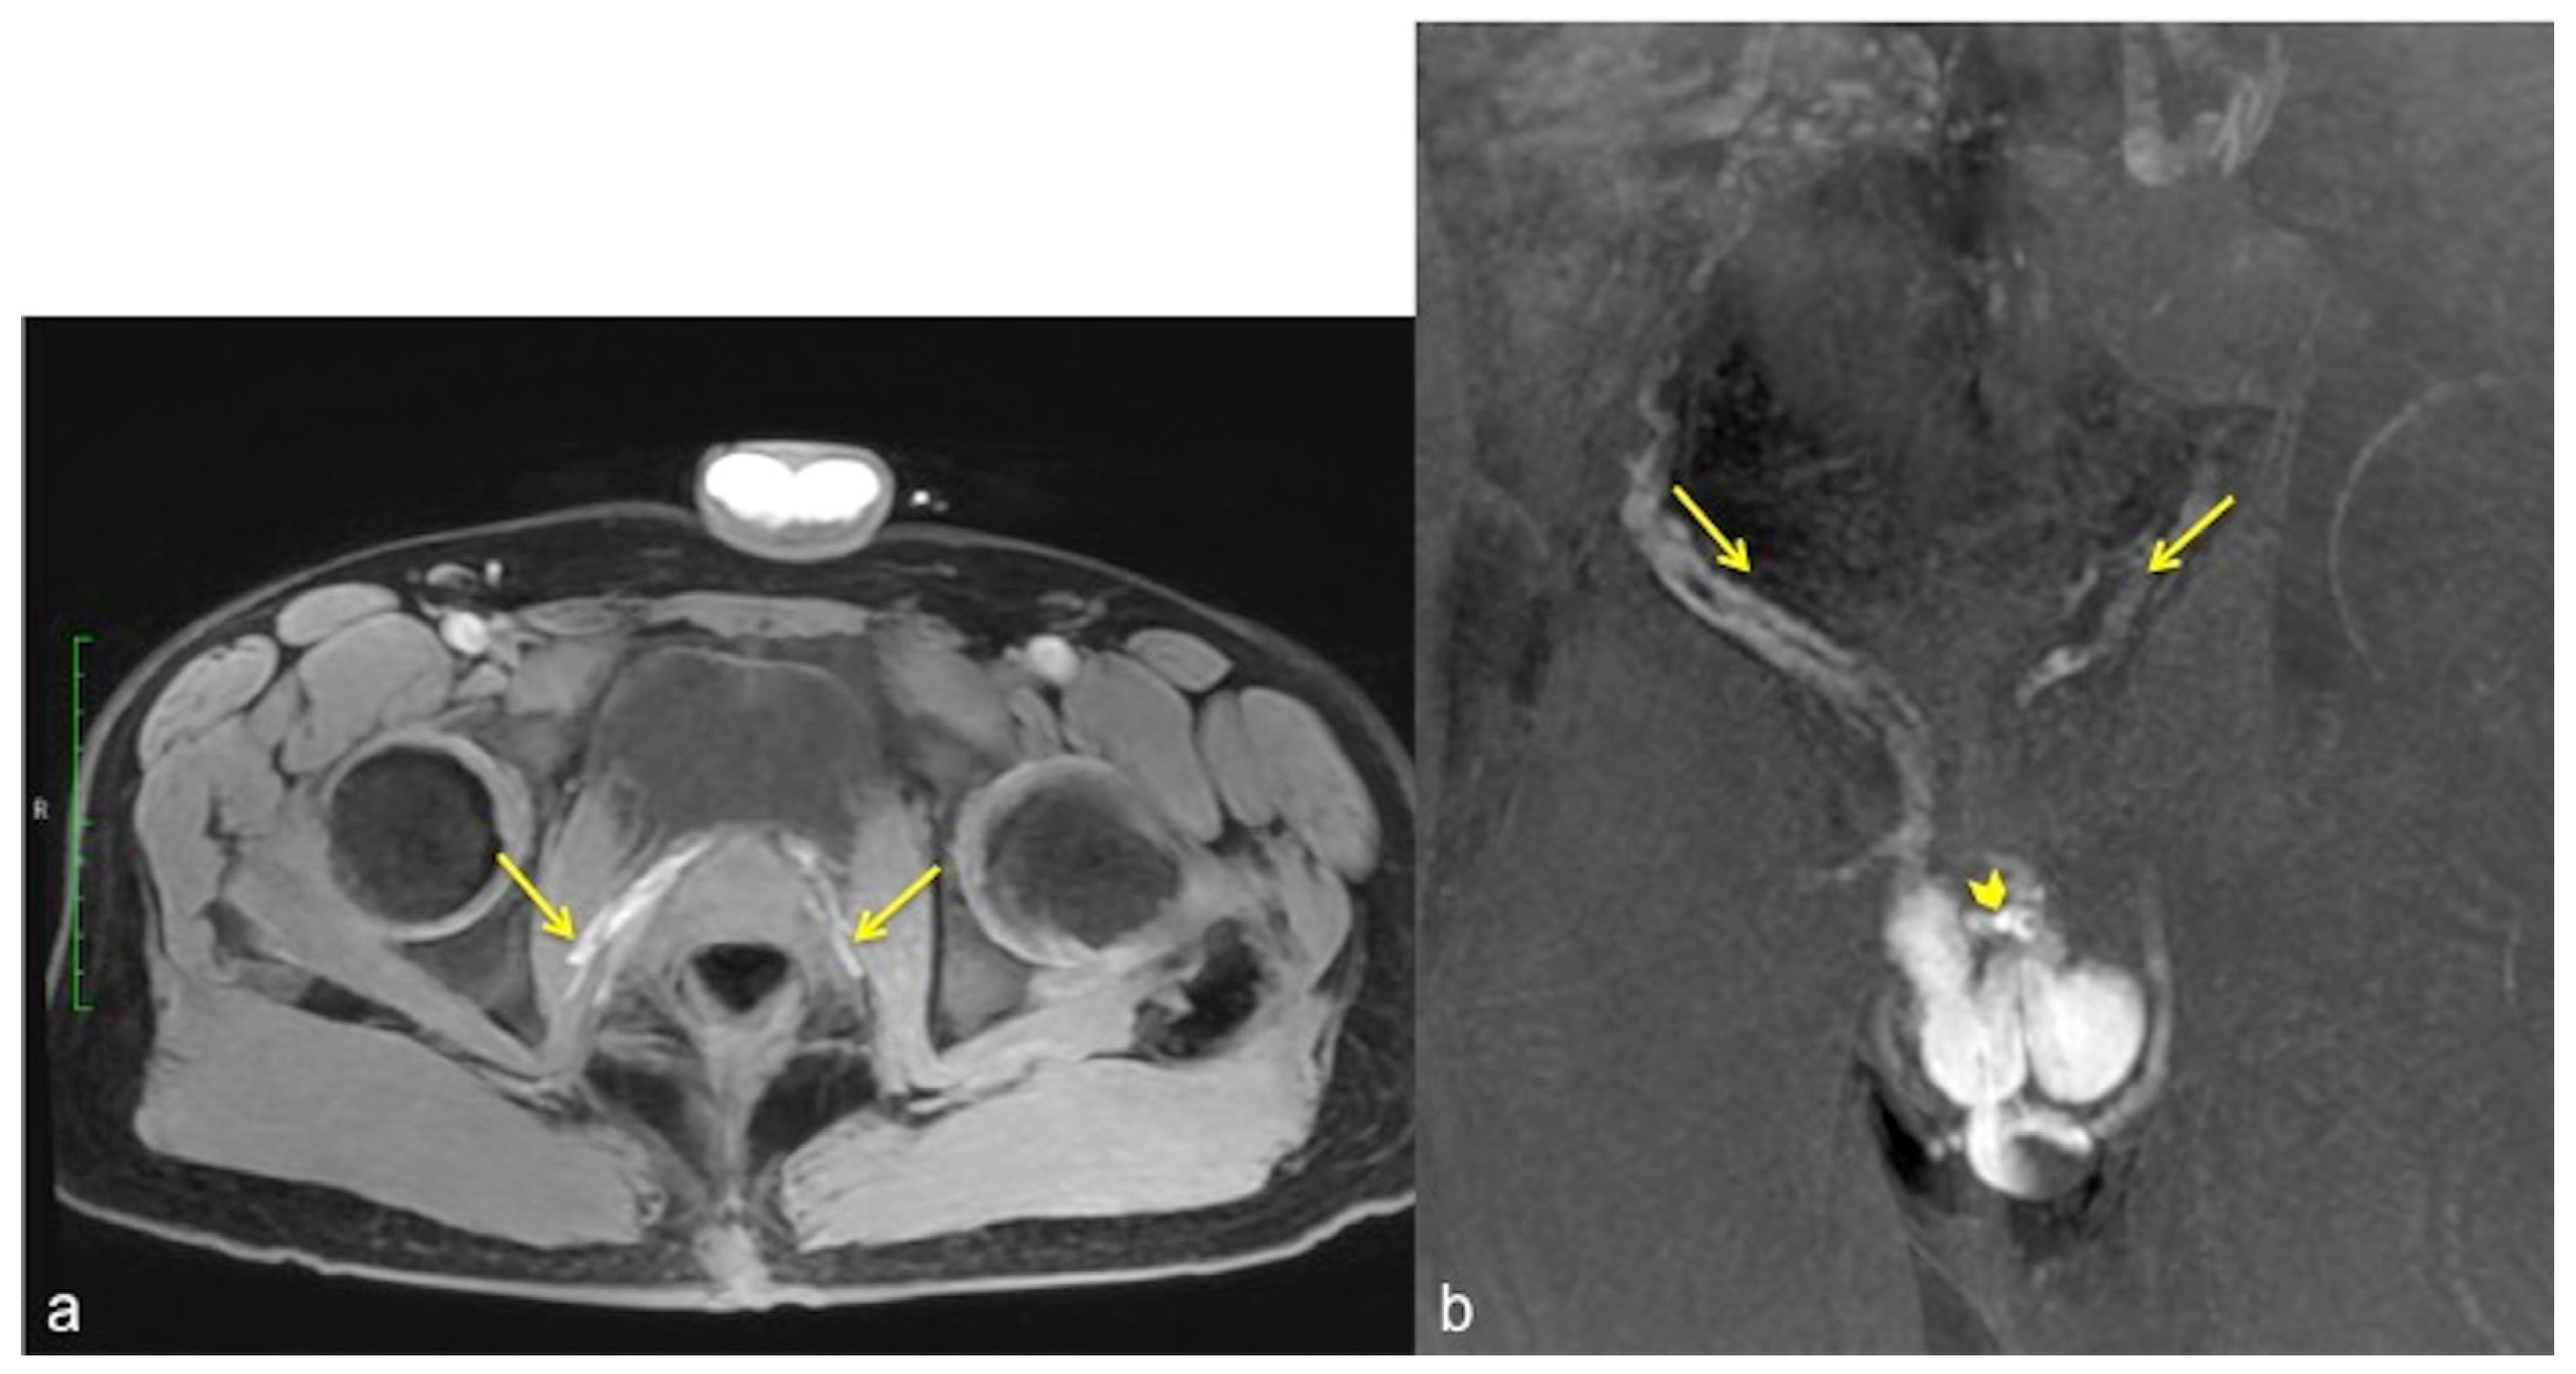

Figure 7.

Cav-MRI. The axial (a) and coronal (b) GRE T1W 3D FS images after contrast agent injection, displayed with MIP reconstruction, show an early opacification of the crural veins ((a), arrows) and of the obturator veins ((b), arrows), supported by venous leakage mediated by the deep dorsal vein of the penis ((b), arrowhead).